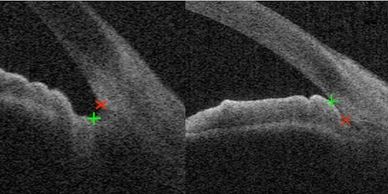

This is an image of a normal ocular angle. The angle is crucial because it serves as the primary pathway for fluid drainage in the eye. Fluid from the front part of the eye drains into the angle and then through the trabecular meshwork, which acts as a filter. This process is vital in preventing conditions such as angle closure and is an important consideration in glaucoma treatment. The fluid then escapes out of veins near the white of the eye, ensuring proper ocular health, especially for those with narrow angles.

At the Inland Glaucoma Center, we provide advanced ocular imaging with OCT, which offers a high-resolution 3D view similar to an MRI of the angle, helping to assess the precise risk of developing angle closure. We also utilize gonioscopy with a mirrored lens, which remains the gold standard in evaluating narrow angles and angle closure.